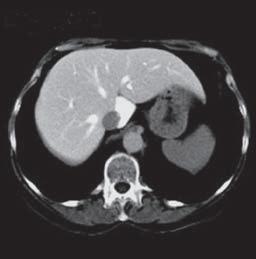

Kazuistika I (segmenty jaterní tkáně)